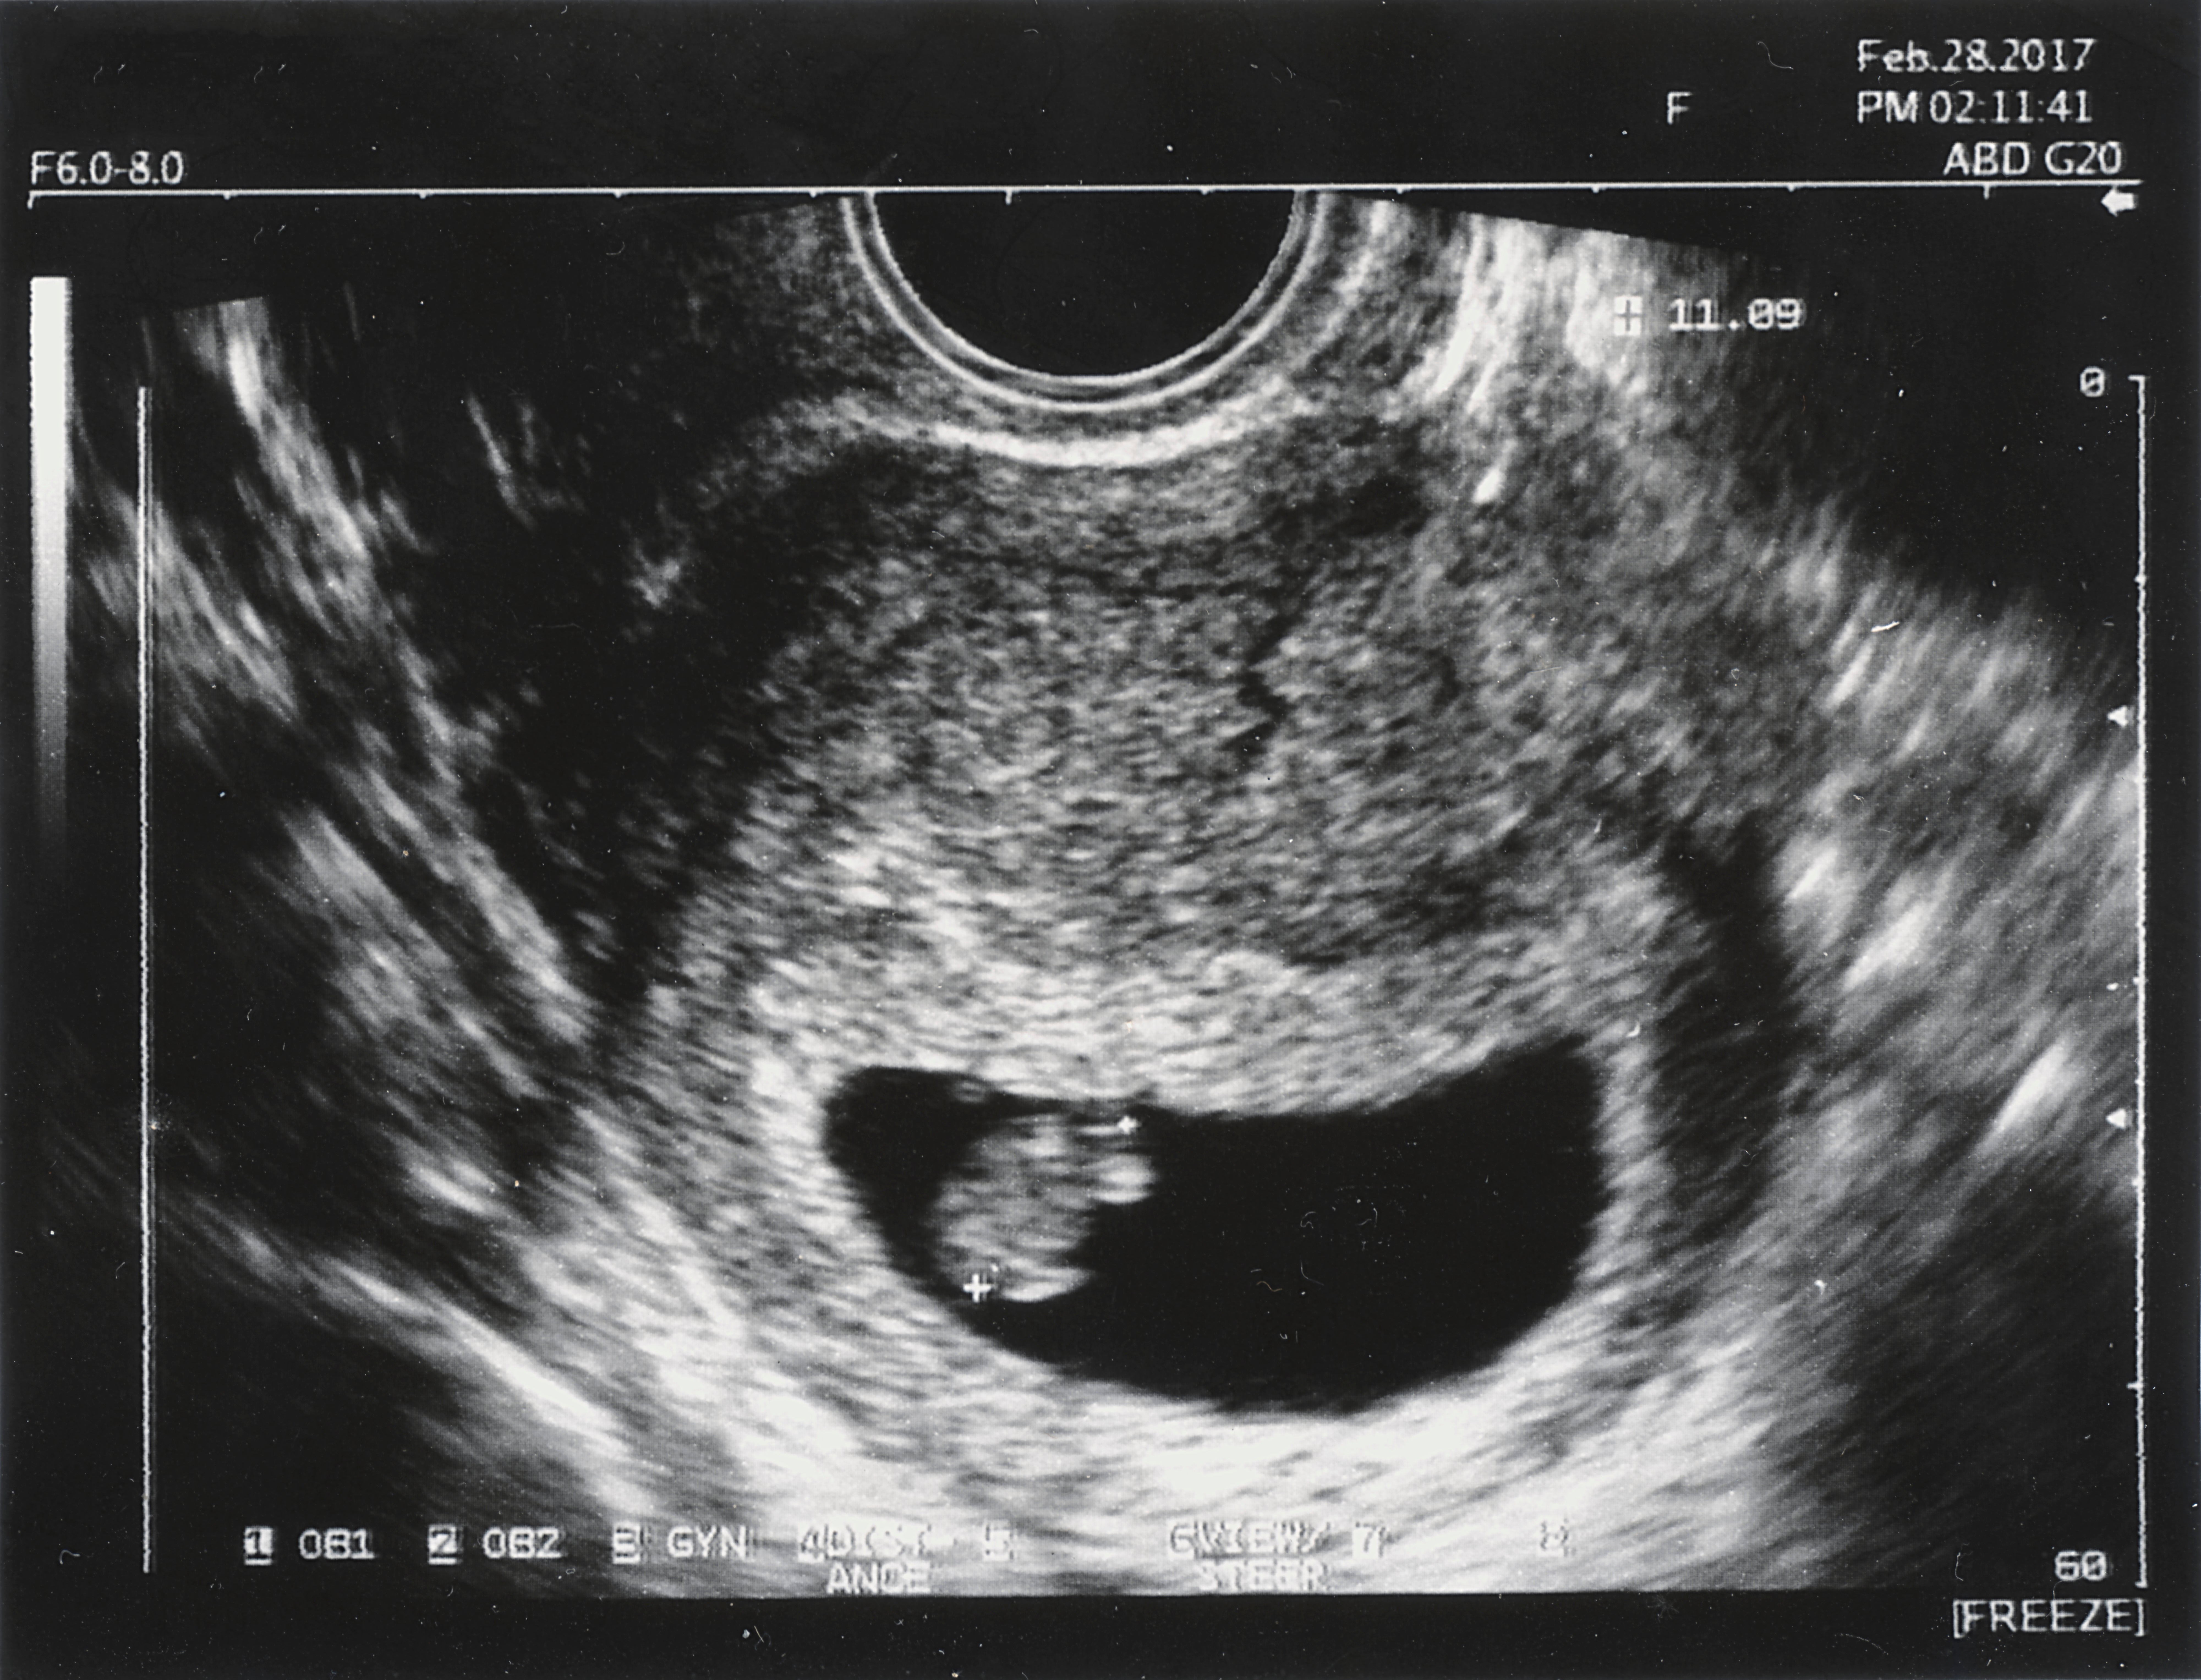

Thailand lockert seine Abtreibungsregeln und erlaubt Frauen künftig einen Abbruch bis zur 20. Schwangerschaftswoche.

Die jetzt im Königlichen Amtsblatt veröffentlichte Änderung soll Ende Oktober in Kraft treten. Schwangere müssen nach der 12. Woche allerdings einen Arzt aufsuchen, sich beraten lassen und eine Genehmigung einholen. Bis dahin dürfen sie eigenständig eine medizinische Einrichtung für einen Abbruch aufsuchen.

Lange waren Abtreibungen in dem buddhistischen Land - außer unter bestimmten Umständen - komplett illegal. Nach einem Urteil des Verfassungsgerichts und einer Änderung des Strafrechts waren sie seit Februar 2021 bis zur 12. Woche möglich. Wer danach einen Abbruch vornehmen ließ, riskierte ebenso eine Gefängnisstrafe wie die Person, die den Eingriff vornahm.